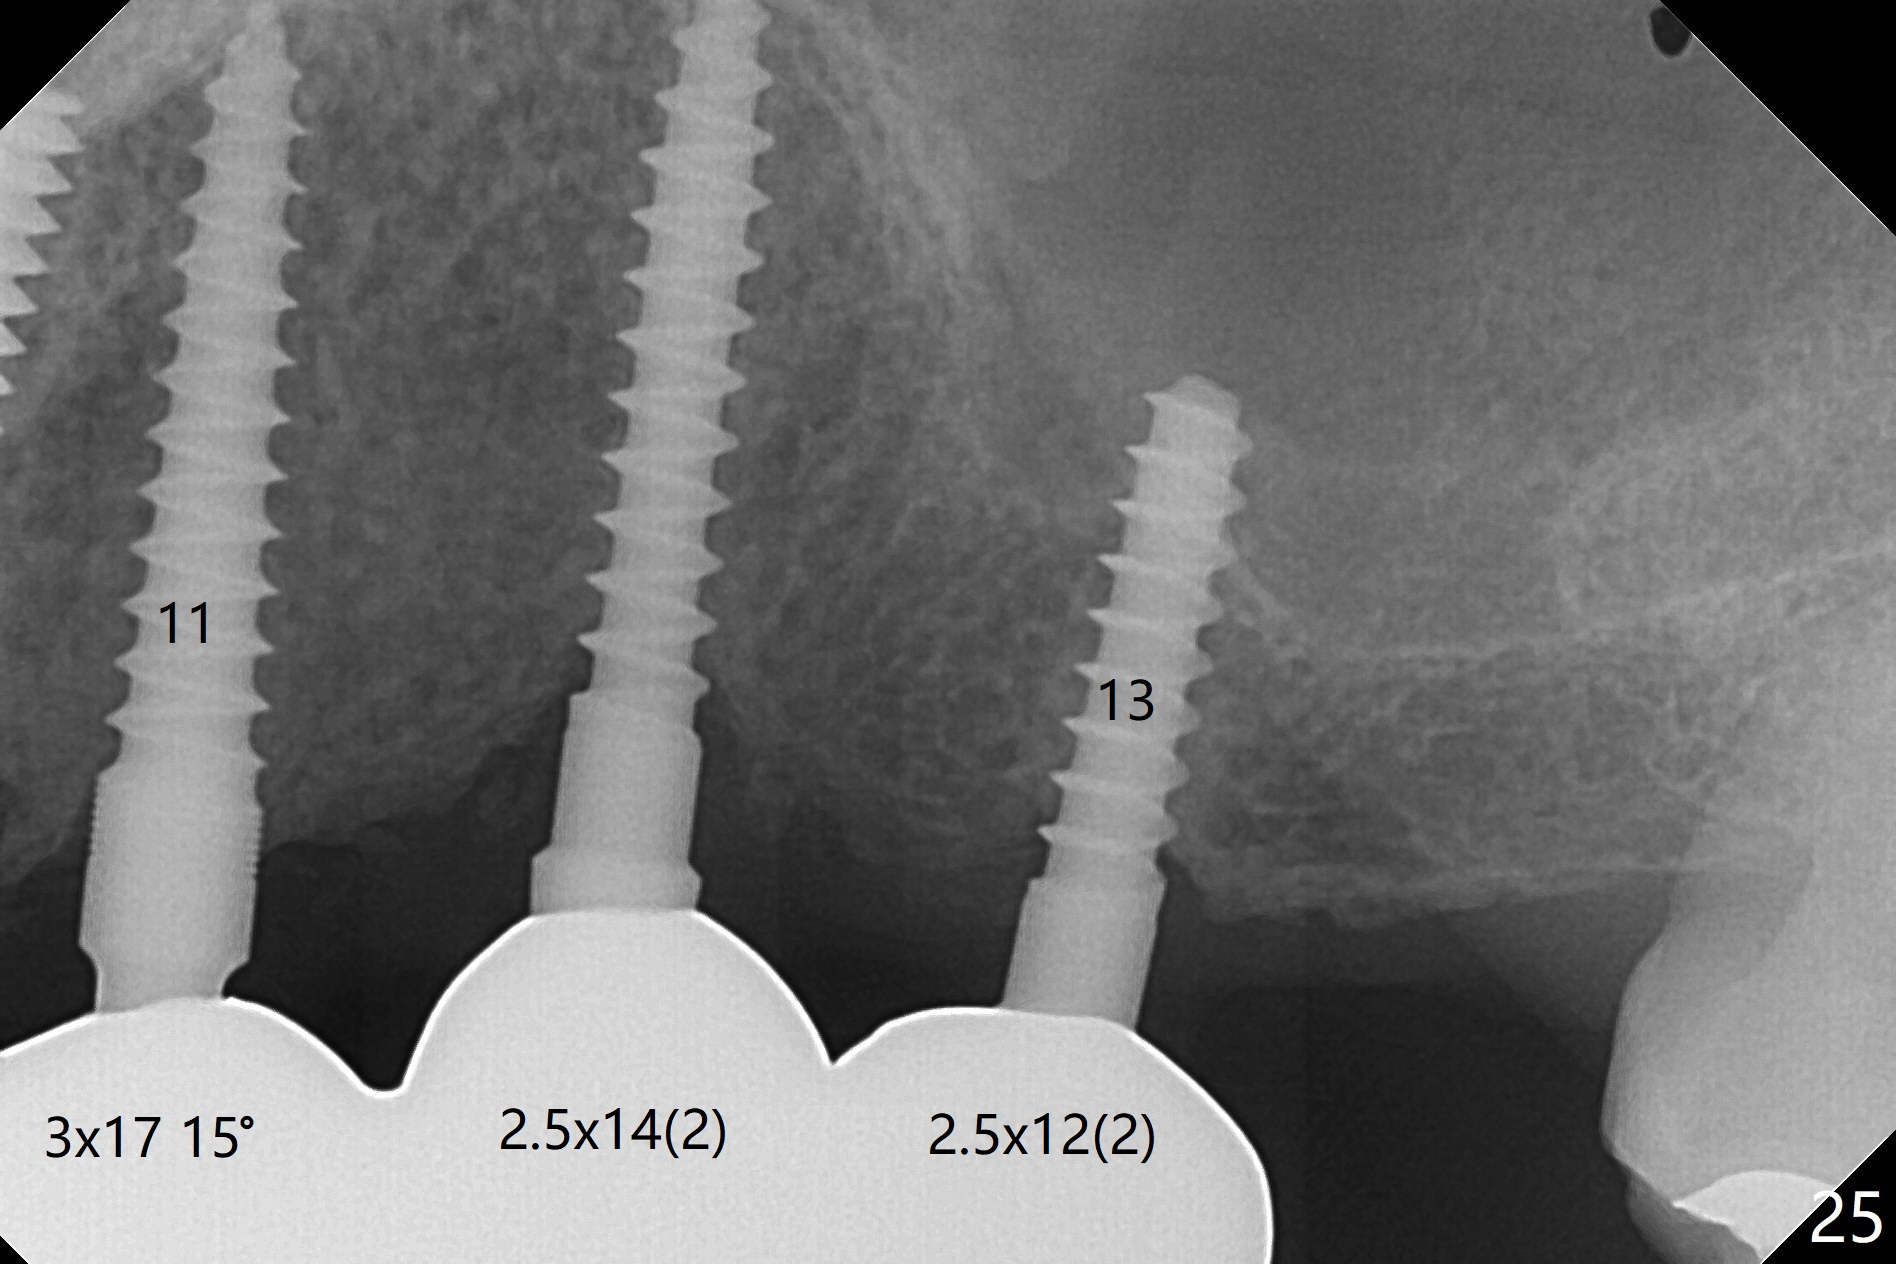

When the patient returns for implant placement (2nd visit after initial exam), he reveals that he is a dental phobic. He requests placement of 4 implants in the upper left quadrant, instead of 2. Narrow ridge is unexpected in the canine and premolar area (Fig.1). Limited bone height at #13 (Fig.3 arrowheads: sinus floor) is found when initial drills are in place (Fig.2,3). A 2-piece implant (4.5x17 mm tissue-level) is placed at #10 after extraction, while 1-piece implants are placed at 11 (3x17 mm (tissue-level, 15 °) and 12 and 13 (bone-level, 2.5x14, 12 mm, respectively; Fig.4,5). In fact the 1 piece implant at #13 is not completely placed (Fig.5). It is removed, the apical 3 threads are cut off (Fig.6 <, since a shorter implant was unavailable in the office) and the remaining implant is re-inserted. The insertion torques of the 4 implants are ~ 60, ~ 35, < 35 and 15 Ncm, respectively. After adjustment (Fig.7), immediate provisionals are fabricated at #10 and 11 (Fig.8, later splinted with composite), while perio dressing is applied around the implants at #12 and 13 and the provisionals at #10 and 11. There is no nasal hemorrhage postop. Although the perio dressing is loose 1 week postop (Fig.9), it is not removed. When the upper lip fissure (Fig.9 <) heals, provisionals at #12 and 13 are planned to be splinted to the other two ones. Two weeks postop, the upper lip fissure heals, the perio dressing dislodges and the implants at #12 and 13 are stable (Fig.10). After abutment height adjustment, a splinted provisional is fabricated over these 2.5 mm 1-piece implants (Fig.11).

Six months post cementation, the tooth #9 becomes symptomatic. Is it possible that the implant at #10 is too close to the root of #9? It is asymptomatic after pulpotomy, but the tooth fractures equi/supragingivally. Two PAs taken while RCT show osteointegration at #10-12 (Fig.18,19). While the bone density increases at #10 regular implant, there is minimal bone loss around the 1-piece implants 13 months post cementation (18 months postop, Fig.20,21). The gingiva remains healthy 19 months post cementation (Fig.22). 76岁病人突然打电话说一个植牙牙冠松动,其实9号牙(自然牙)折裂,6,10-13号牙植牙好像没有骨质吸收(图二十三至二十五),10-13牙位牙龈健康(图二十六,行使功能五年)。9号牙牙冠重新粘固后,显示前牙深覆合,深覆盖(图二十七,二十八)。如果再次脱落需要植牙,选择一段式有助于植入和修复,因为植体和基台直径小。两段式植牙相对基台直径至少4,或者4.5毫米,前牙修复显得笨重。由于9,10牙根和植体接近,9号牙植体需要偏小而长,3x14或者15毫米(图二十九)。